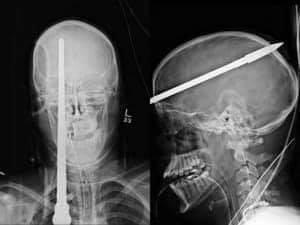

Tunus'ta yaşayan 23 yaşındaki Hazim Karar isimli bir zıpkıncı arkadaşımız havalı tüfeğinin bakımını yaparken yaşanan bir kaza sonucunda üzücü bir şekilde vefat etti.

11.09.2019 Çarşamba günü yaşanan vahim kazada bakımını yaptığı havalı tüfekten çıkan şişin, Hazim Karar' ın gözüne isabet ederek yaralanmasına neden olduğu, hastaneye kaldırılan Hazim Karar'ın 12.09.2019 Perşembe akşamı yaşamını yitirdiği haberi geldi. Hobidaşımızın ailesine ve sevdiklerine baş sağlığı diliyoruz.